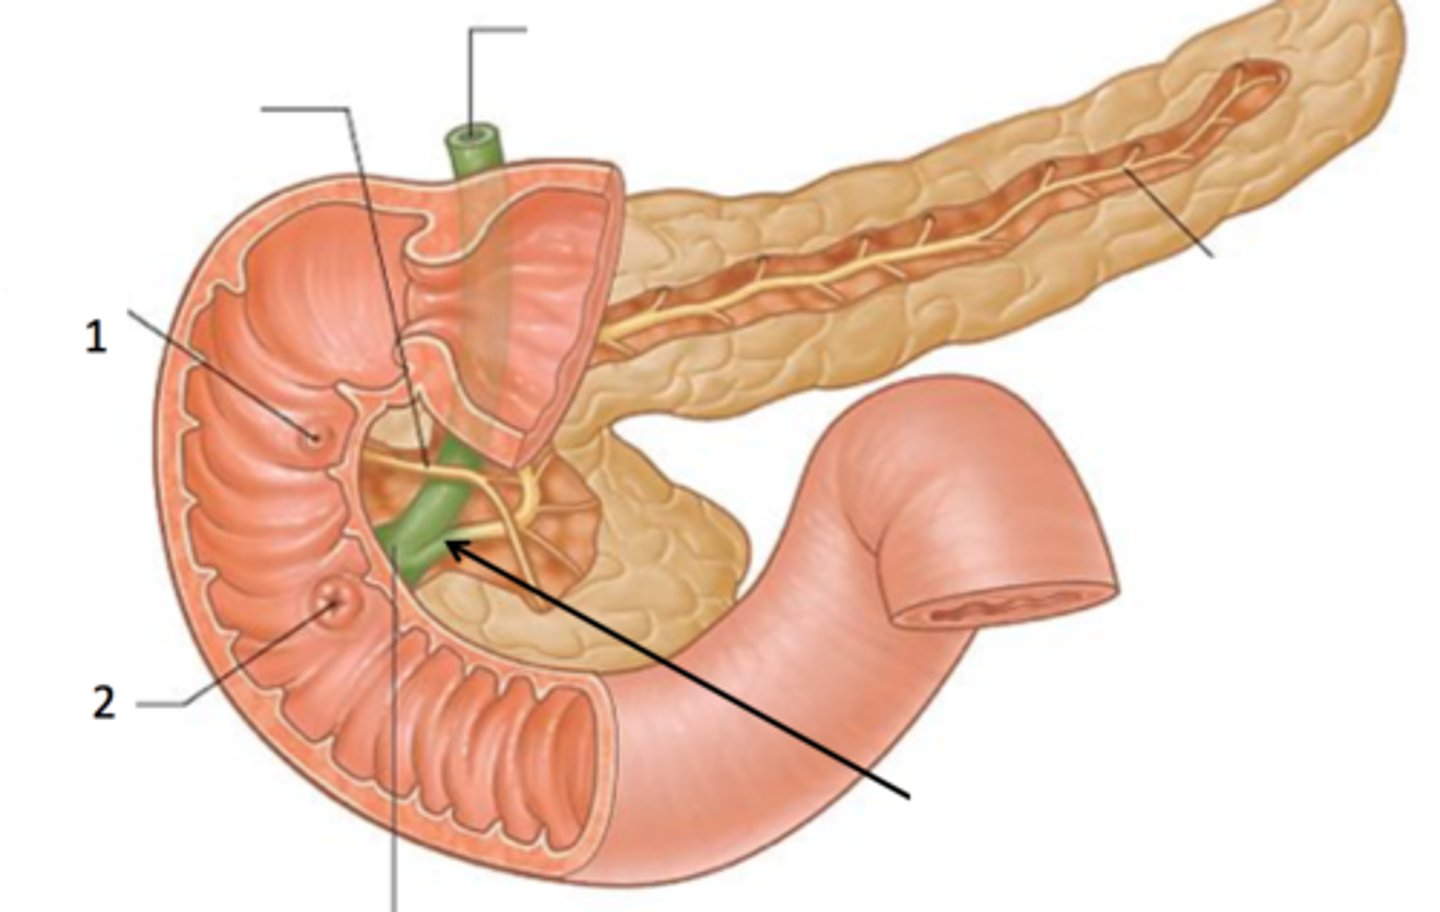

duodenum

A

major duodenal papilla

exit of hepatopancreatic duct

minor duodenal papilla

- #1

- exit for accessory pancreatic duct